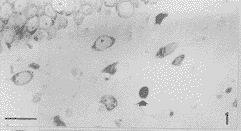

海马齿状回门区(图1)KA后1d,仅偶见凋亡神经元;KA后3d,可见较多的凋亡细胞;KA后5d凋亡细胞数目最多;KA后7d,该区凋亡神经元的数目已开始减少。

图1 KA3d后,海马齿状回门区内的凋亡神经元(↑)。标尺示3μm

Fig. 1 An apoptoiic neuron in dentate hilus(↑) . 3d after KA iniection. Bar=30μm